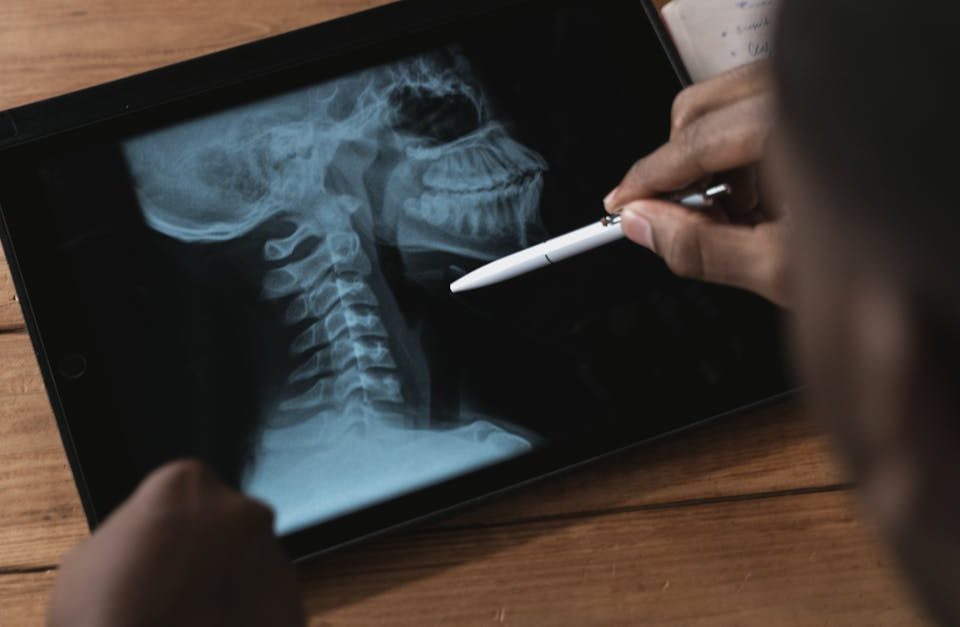

Les étapes pour établir un diagnostic précis de sténose spinale avant de commencer un traitement

EN BREF En résumé, la sténose spinale est un rétrécissement du canal rachidien qui peut entraîner des douleurs et des problèmes de mobilité. Le processus de […]